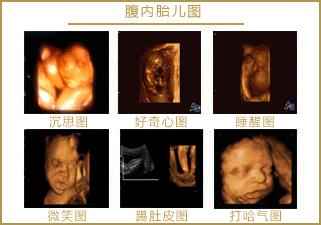

苗苗怀孕5个半月的时候去做四维彩超,她一直注视着大屏幕上宝宝的一举一动。忽然,她看到胎宝宝咧嘴笑了,这给她大大的惊喜,同时,她又很惊讶,宝宝在肚子里也会笑?常听说宝宝出生后还不会笑呢?

医生说:很正常,我们做四维彩超经常看到有宝宝笑。苗苗才知道自己是少见多怪了,而医生见的多了觉得稀松平常。

其实,关于胎宝宝在肚子里微笑,类似的报道并不少见,很多妈妈反馈过做四维时看到宝宝笑的样子,国外媒体也经常报道类似的新闻。

怀孕5个半月,胎儿已经有了面部表情,喜怒哀乐都会有,当然胎儿也会发笑。

胎儿的听力能力进一步发展,对外界的声音极其敏感,当听到喜欢的音乐、妈妈温柔的声音时,胎儿会用微笑表示开心。所以,妈妈要多听一些美妙的音乐、多和宝宝说话,让宝宝感受到幸福,出生后也会笑得更美好。

从这里看出,在做四维彩超的时候很容易捕捉到胎儿的微笑,这时不要觉得奇怪,这是胎儿正常的生理反应。